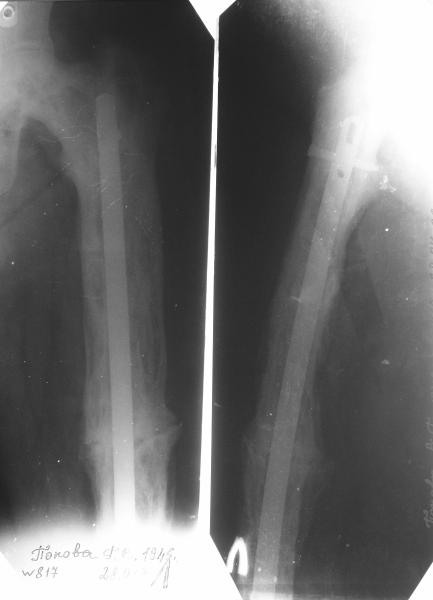

Пациент 82 лет, поступил через 5 мес. с несросшимся переломом после открытого интрамедуллярного остеосинтеза. Выполнили реостеосинтез стержнем 12 мм. ( мах. доступного нам в 2003 г.) Через 4 мес динамизация. В течении 2х лет сращения нет, тем не менее конечность опорна (ходит с тростью). От очередного реостеосинтеза отказались из-за сопутств. патологии.

PS: случай конечно не аналогичный, учитывая первичный открытый остеосинтез.